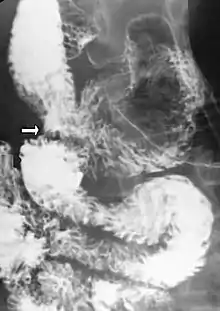

Upper gastrointestinal series showing duodenojejuonostomy (white arrow).

If medical treatment fails, or is not feasible due to severe illness, surgical intervention is required. The most common operation for SMA syndrome, duodenojejunostomy, was first proposed in 1907 by Bloodgood.[7] Performed as either an open surgery or laparoscopically, duodenojejunostomy involves the creation of an anastomosis between the duodenum and the jejunum,[23] bypassing the compression caused by the AA and the SMA.[1] Less common surgical treatments for SMA syndrome include Roux-en-Y duodenojejunostomy, gastrojejunostomy, anterior transposition of the third portion of the duodenum, intestinal derotation, division of the ligament of Treitz (Strong's operation), and transposition of the SMA.[24] Both transposition of the SMA and lysis of the duodenal suspensory muscle have the advantage that they do not involve the creation of an intestinal anastomosis.[9]